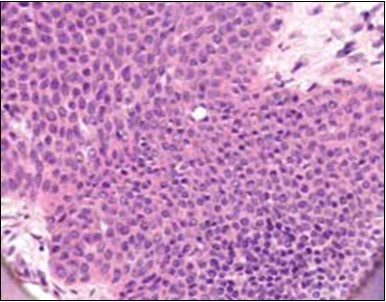

Granular arrangement of malignant cells and intercellular bridges are conspicuous with the demonstration of nuclear atypia, pleomorphism, prominent mitosis and tumour necrosis. A peripheral palisade is discernible within the cellular aggregates. Mitotic figures are common and can be quantified as up to 12 mitosis/ high power field. Tumour differentiation can prominently be of the ductal category with the demonstration of intra-cytoplasmic lumina. Comedo type tumour necrosis is evident along with foci of squamous differentiation The neoplasm is reactive to periodic acid Schiff ‘s (PAS) stain. (Figure 1, Figure 2, Figure 3, Figure 4, Figure 5, Figure 6, Figure 7, Figure 8, Figure 9, Figure 10, Figure 11, Figure 12, Figure 13.

Figure 4.Cellular atypia, mitosis and focal necrosis in eccrine porocarcinoma(16).